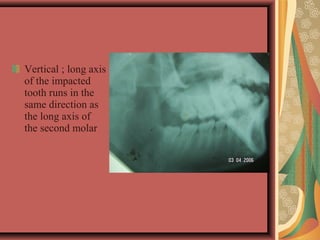

Vertical ; long axis

of the impacted

tooth runs in the

same direction as

the long axis of

the second molar